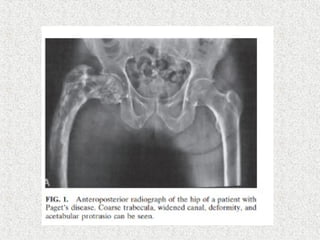

 Severe disabling arthritis

 THR

 Significant varus deformity

 Bowing

 Acetabular protrusion

 Increased blood loss

 Distorted medullary cavity

 Sclerosis

 Heterotrophic ossification